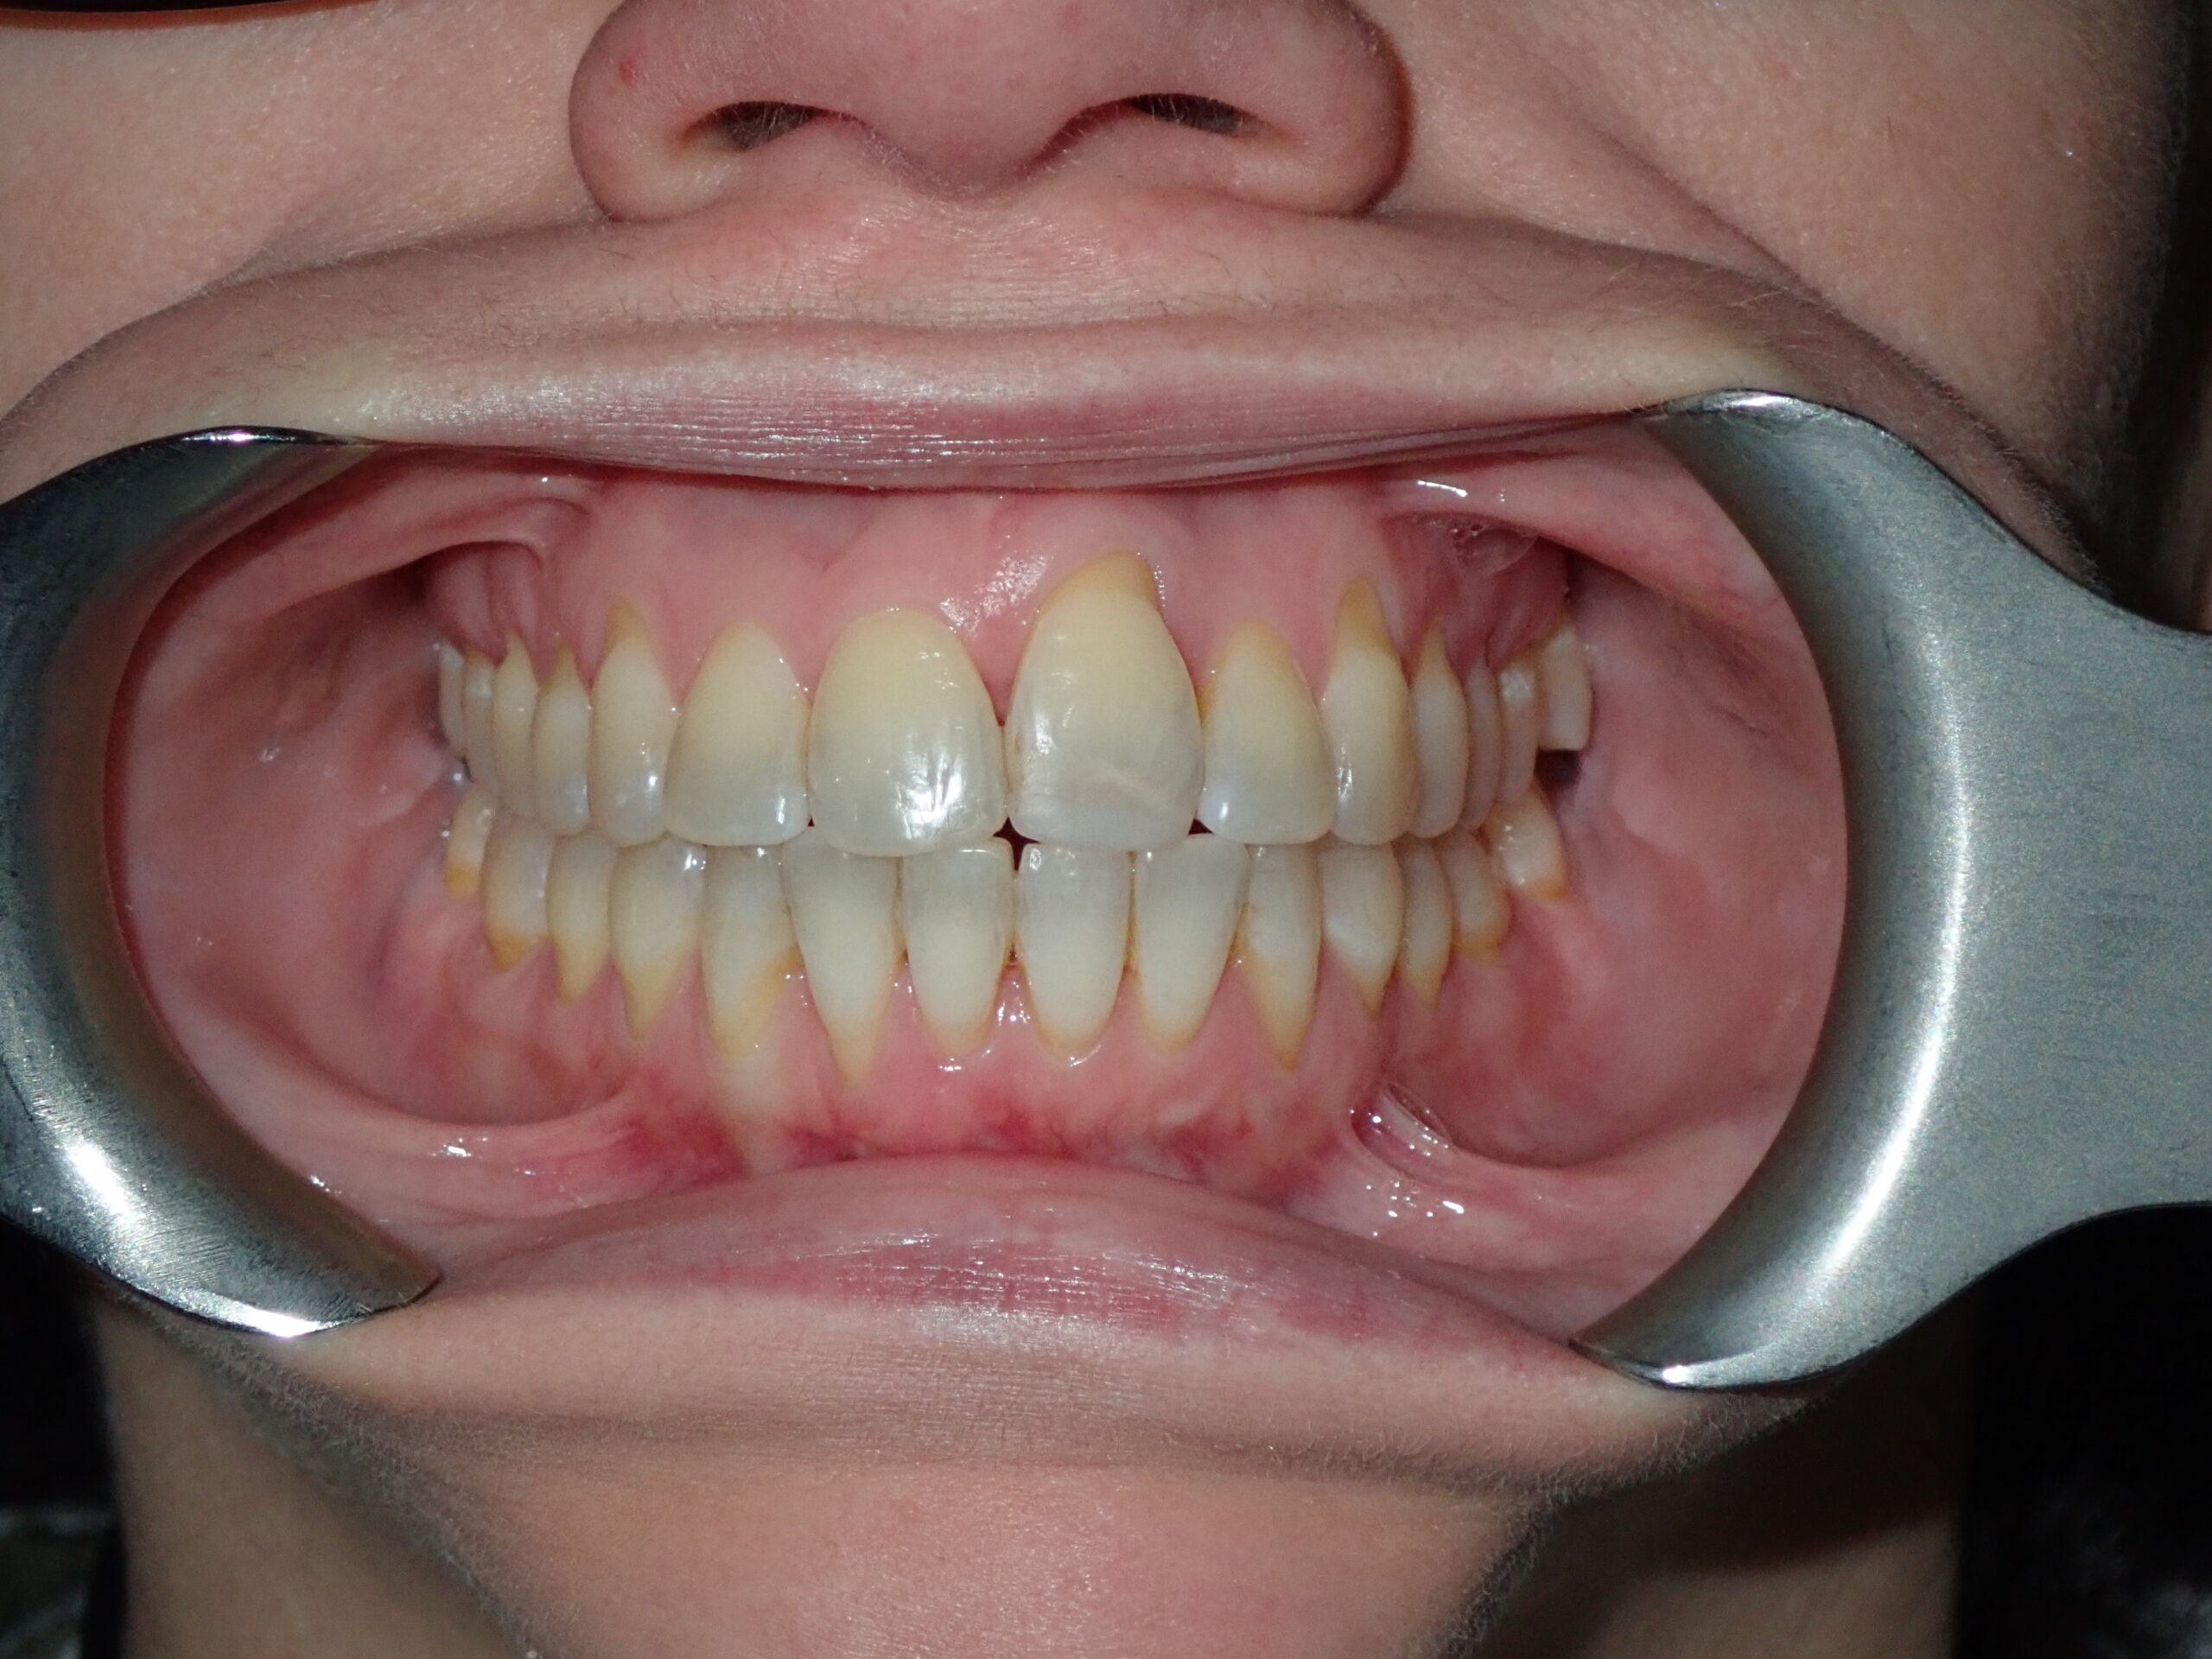

Imagine a Perfect Smile.تخيّل ابتسامةً مثالية.

Airway-centred orthodontics aligns teeth while expanding jaw structure — creating a broader smile, better breathing, and lasting facial harmony without surgery.تقويم الأسنان المتمحور حول الهوائي يُقوّم الأسنان مع توسيع بنية الفك — ابتسامة أوسع وتنفس أفضل وانسجام وجهي دائم بدون جراحة.

Patient Resultsنتائج المرضى

Real Results. Real Patients.نتائج حقيقية. مرضى حقيقيون.